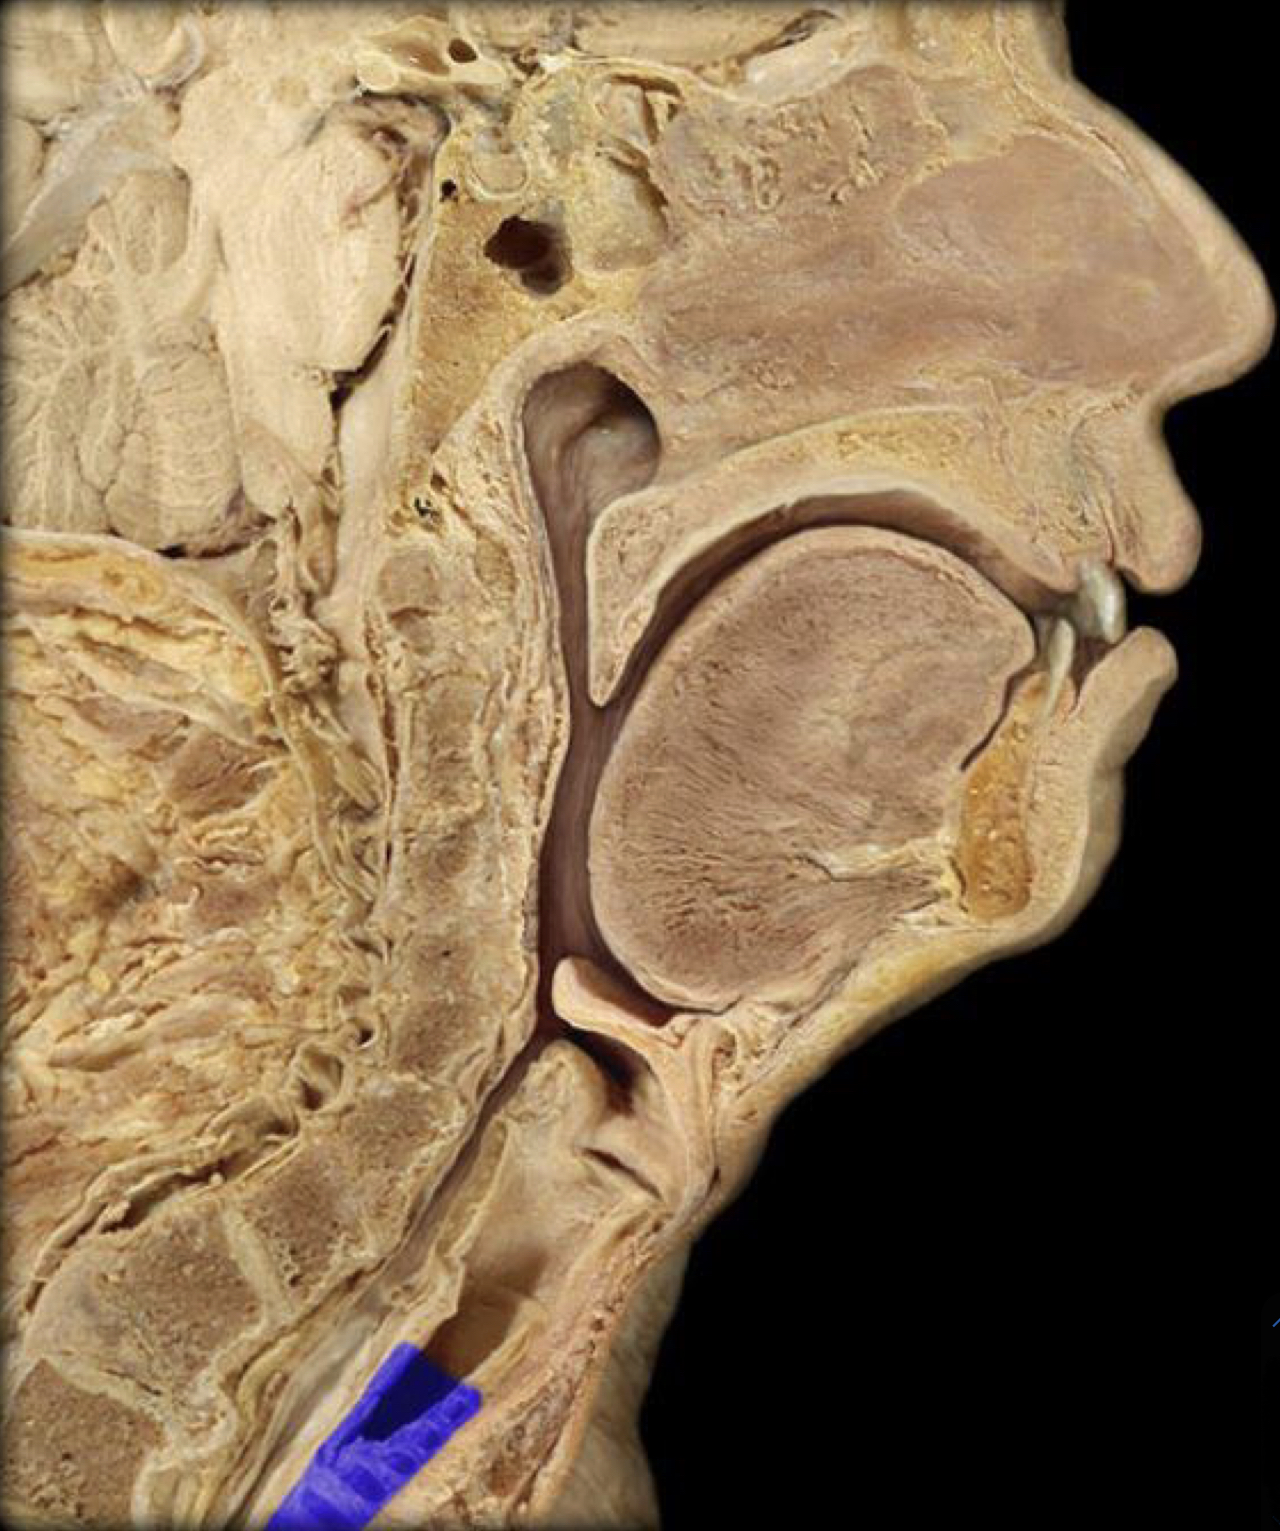

What structure is highlighted in blue?

Nasopharynx